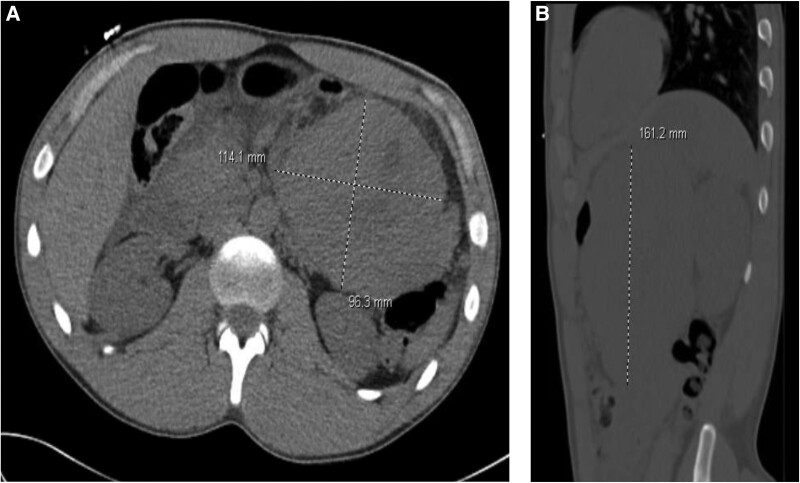

高钙血症可由多种病因引起,最常见的是原发性甲状旁腺功能亢进。虽然原发性甲状旁腺功能亢进是一种相对常见的内分泌疾病,但异位甲状旁腺激素分泌是一种罕见的疾病,在文献中描述较少。我们描述的第一个病例严重,症状性高钙血症发现继发于甲状旁腺激素分泌胰腺母细胞瘤。患者最初表现为疲劳和进行性上肢间歇性肌肉抽搐。他被发现有原发性甲状旁腺功能亢进的生化证据。颈部的计算机断层扫描和sestamibi核扫描未能明确显示甲状旁腺腺瘤或增生,双侧手术甲状旁腺探查未发现任何病理。通过计算机断层扫描获得腹部成像以评估术后进行性胃脘痛,患者发现腹膜后肿块,经活检诊断为胰腺母细胞瘤。该肿块被切除,导致术中PTH值下降,术后继发于饥饿骨综合征的低钙血症。随访后,患者甲状旁腺功能恢复,补钙和维生素D的剂量可逐渐减少。异位甲状旁腺激素分泌团块是一种罕见的实体,但在病因不明的难治性原发性甲状旁腺功能亢进患者中应予以考虑。

Hypercalcemia may be induced by a variety of etiologies, most commonly primary hyperparathyroidism. Although primary hyperparathyroidism represents a relatively common endocrinological disorder, ectopic PTH secretion is a rare entity that is less well described in literature. We describe the first case to our knowledge of severe, symptomatic hypercalcemia found to be secondary to a PTH-secreting pancreatoblastoma. The patient initially presented with fatigue and progressive upper extremity intermittent muscular twitching. He was found to have biochemical evidence of primary hyperparathyroidism. A computed tomography scan of the neck and a sestamibi nuclear scan failed to definitively demonstrate a parathyroid adenoma or hyperplasia and bilateral surgical parathyroid exploration was unrevealing for any pathology. Abdominal imaging via computed tomography was obtained for evaluation of progressive postoperative epigastric pain, and the patient was found to have a retroperitoneal mass that, after biopsy, was diagnostic for a pancreatoblastoma. This mass was resected resulting in a fall in intraoperative PTH values and subsequent postoperative hypocalcemia secondary to hungry bone syndrome. Upon follow-up, the patient's parathyroid function recovered and doses of supplemental calcium and vitamin D could be tapered. Ectopic PTH-secreting masses represent a rare entity but should be considered in individuals with unclear etiology of recalcitrant primary hyperparathyroidism.